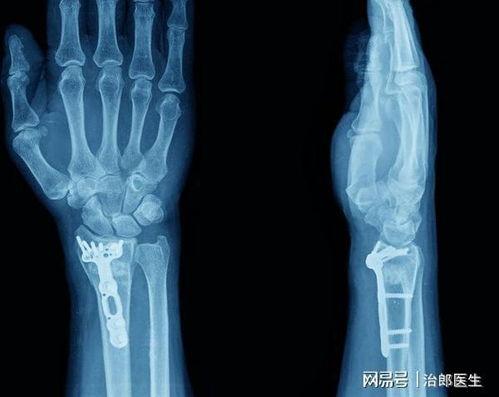

对于普通CT检查,如头部、胸部、骨骼或四肢等部位的检查,通常不需要特别的饮食限制。患者可以正常进食,但建议避免在检查前短时间内进食,以免影响检查的舒适度。